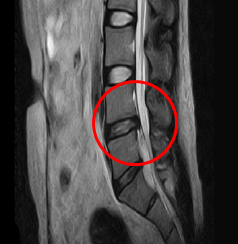

요추 추간판 수핵탈출증의 단계

팽륜

돌출

탈출

전위